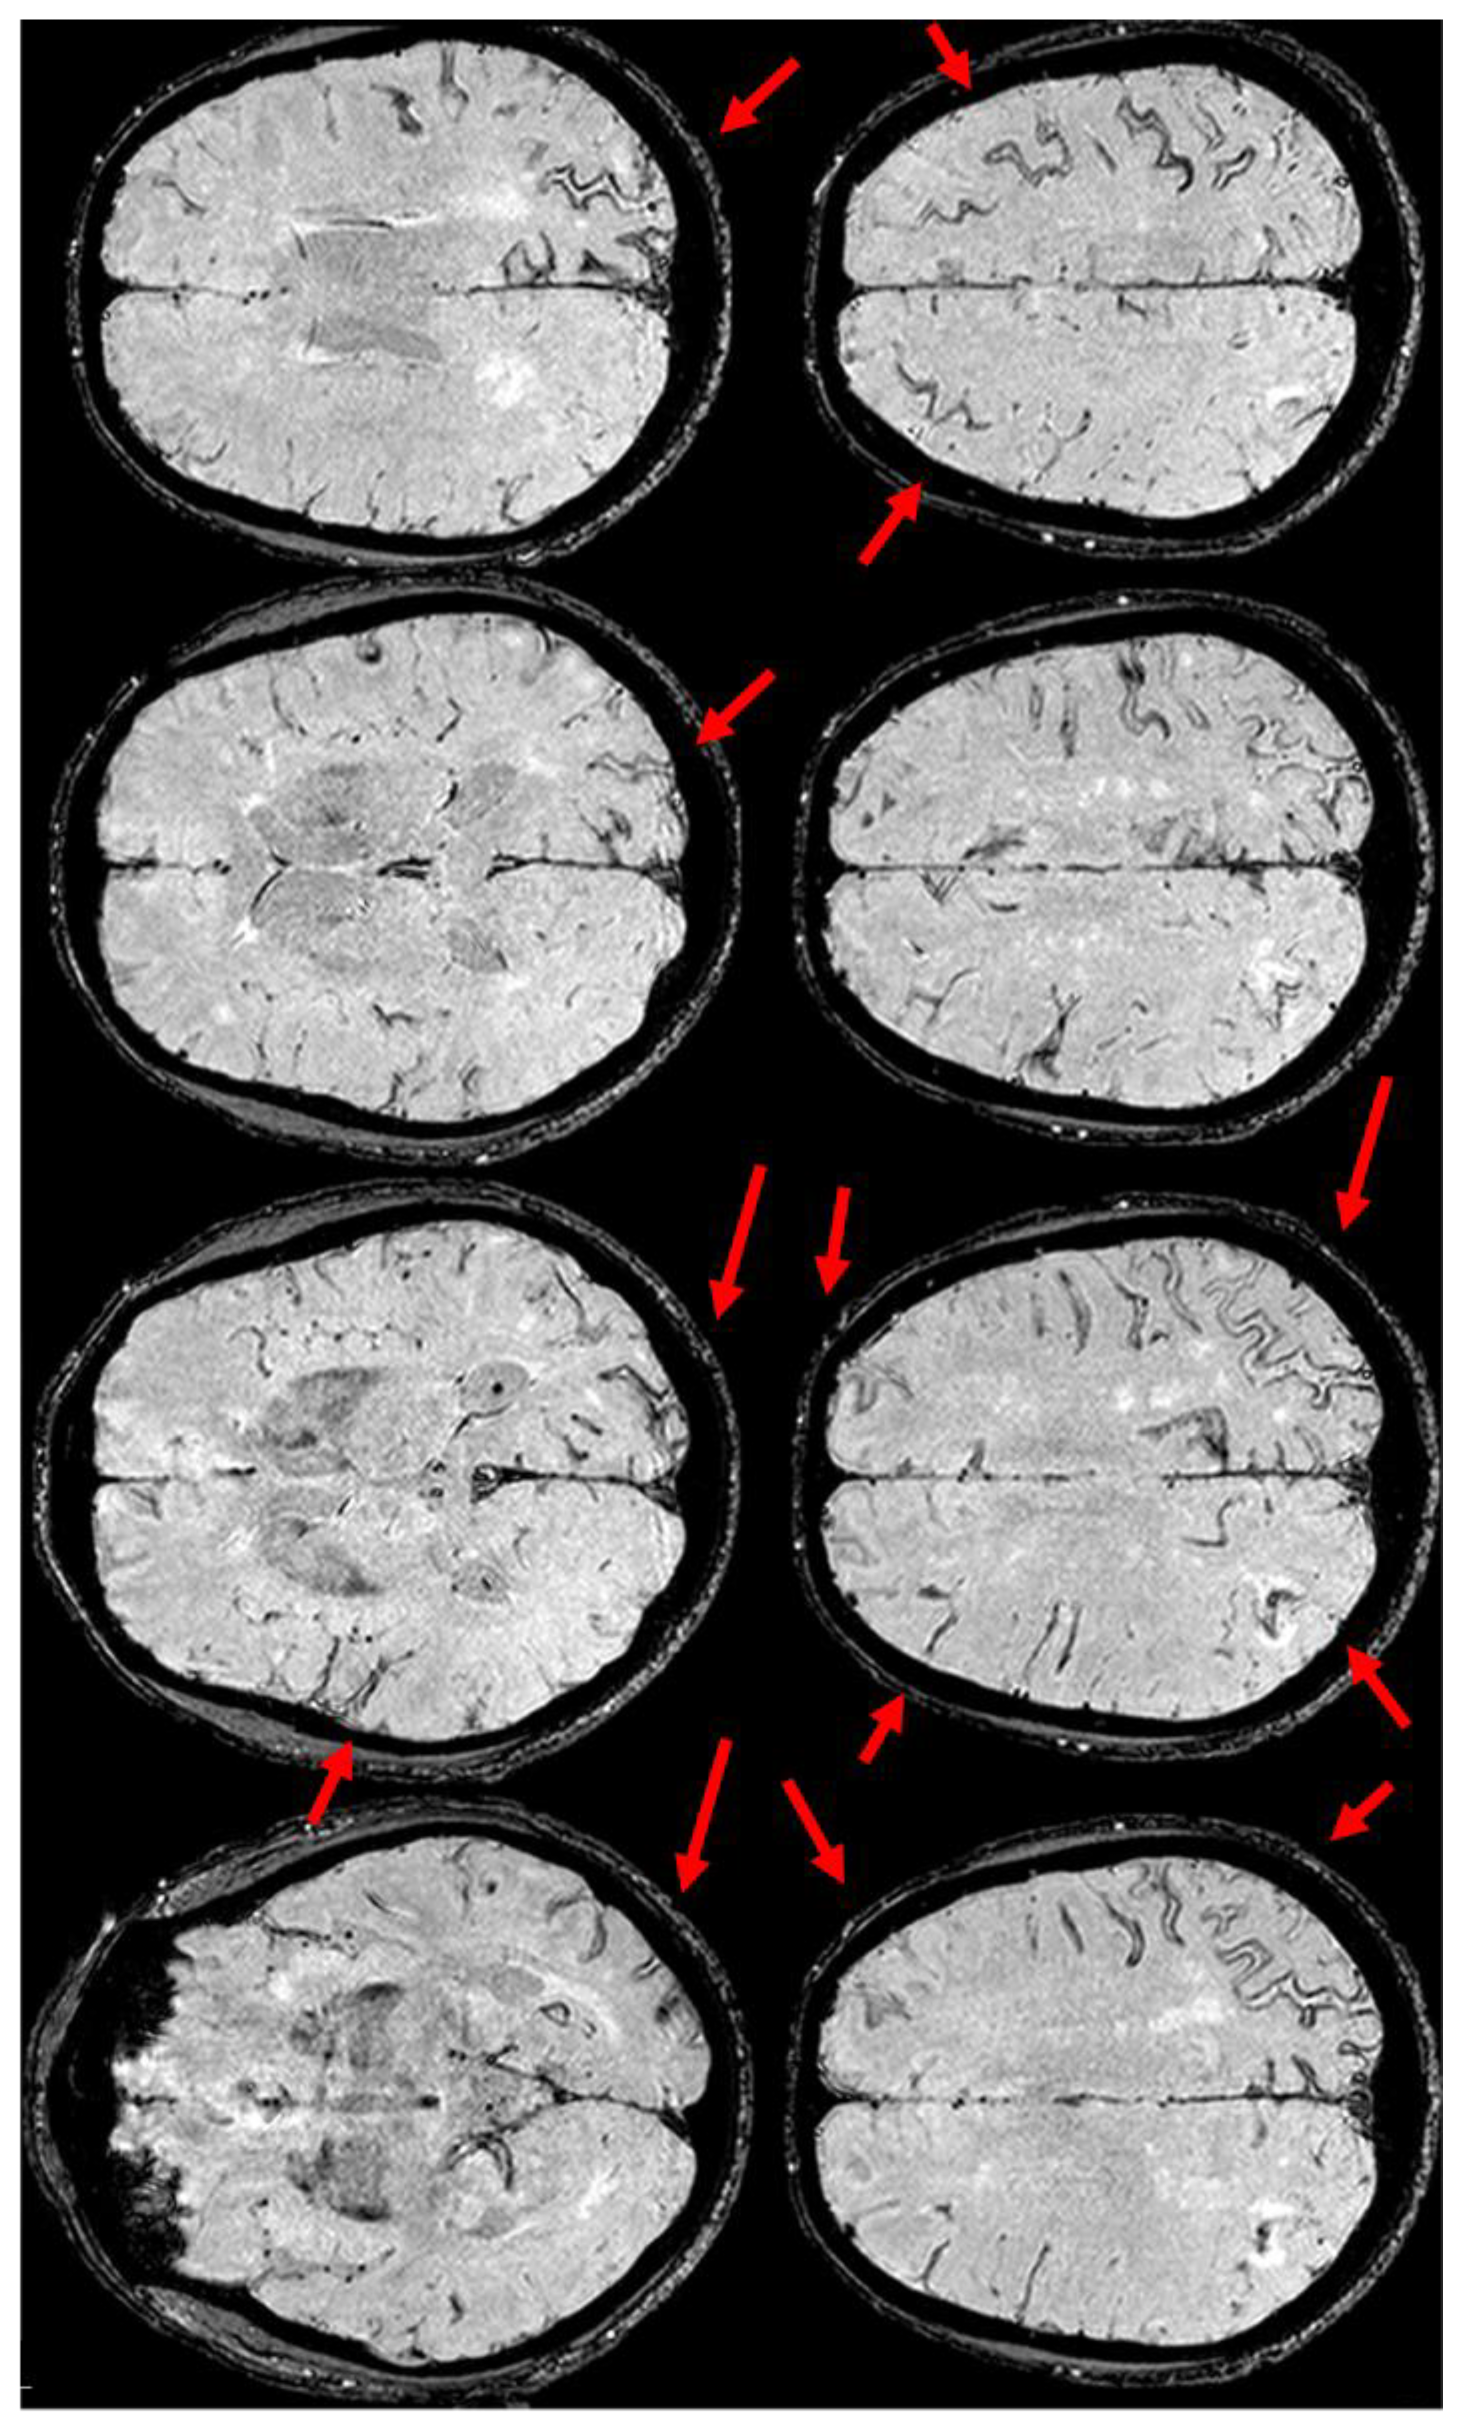

6. December 2017: Recurrent SAH